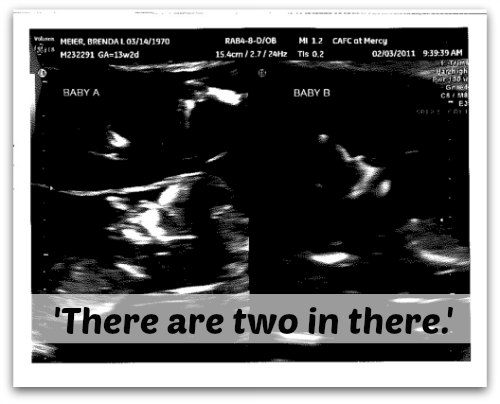

Then she leaned down near me and whispered, “There are two in there.”

And she proceeded to show me two little blinking lights on the monitor. First one, then the other. Then both of them together on the screen–to prove she wasn’t lying.

And exactly six months later those two little blinking lights on the ultrasound monitor were born.